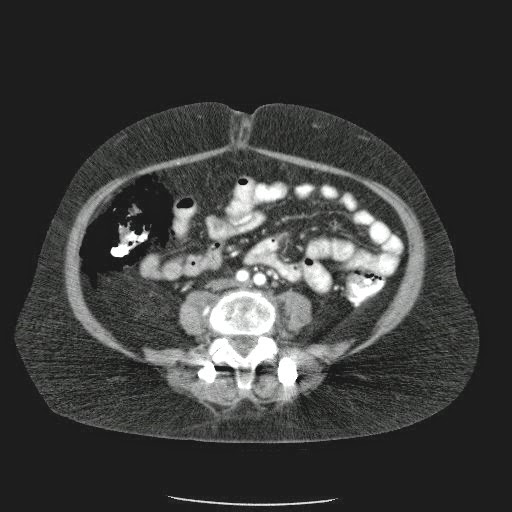

- ¿Hallazgos Escanografia?

2. Hay una colección de la pared abdominal en el flanco derecho, que realza en la periferia con el contraste, e intraabdominal tiene aire pero no me parece colección intraabdominal porque la grasa no está alterada.

3. Recomendado: Drs. JOSÉ M. ZUÑIGA A.1, FRANCO ORELLANA G.1, MARCELO CASTRO S.3, ROLANDO SEPÚLVEDA D.4, HORACIO RÍOS R.4, Int. VELIA SALDÍAS H.2. Neumatosis Intestinal: Caso Clínico-Radiológico. Pneumatosis intestinalis. A case report. Rev Chil Cir v.61 n.1 Santiago feb. 2009